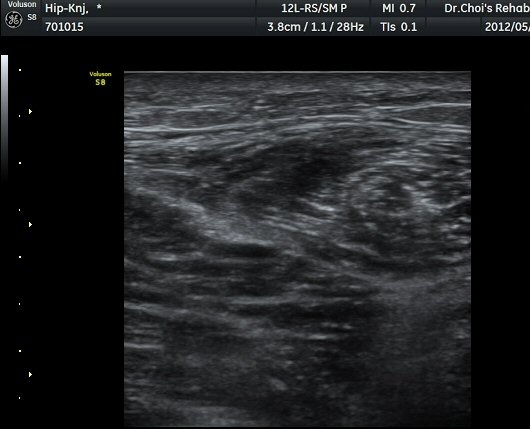

ŽÃËÀÚ¸¦ ¾Æ·¡·Î À̵¿ÇÏ´Ï ´ëÅðÁ÷±Ù³»¿¡ Àú¿¡ÄÚ º¯º¯ÀÌ °üÂûµÈ´Ù(±×¸² 2, 3).